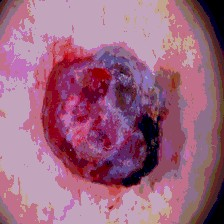

Timely identification and treatment of rapidly progressing skin cancers can significantly contribute to the preservation of patients' health and well-being. Dermoscopy, a dependable and accessible tool, plays a pivotal role in the initial stages of skin cancer detection. Consequently, the effective processing of digital dermoscopy images holds significant importance in elevating the accuracy of skin cancer diagnoses. Multilevel thresholding is a key tool in medical imaging that extracts objects within the image to facilitate its analysis. In this paper, an enhanced version of the Mud Ring Algorithm hybridized with the Whale Optimization Algorithm, named WMRA, is proposed. The proposed approach utilizes bubble-net attack and mud ring strategy to overcome stagnation in local optima and obtain optimal thresholds. The experimental results show that WMRA is powerful against a cluster of recent methods in terms of fitness, Peak Signal to Noise Ratio (PSNR), and Mean Square Error (MSE).